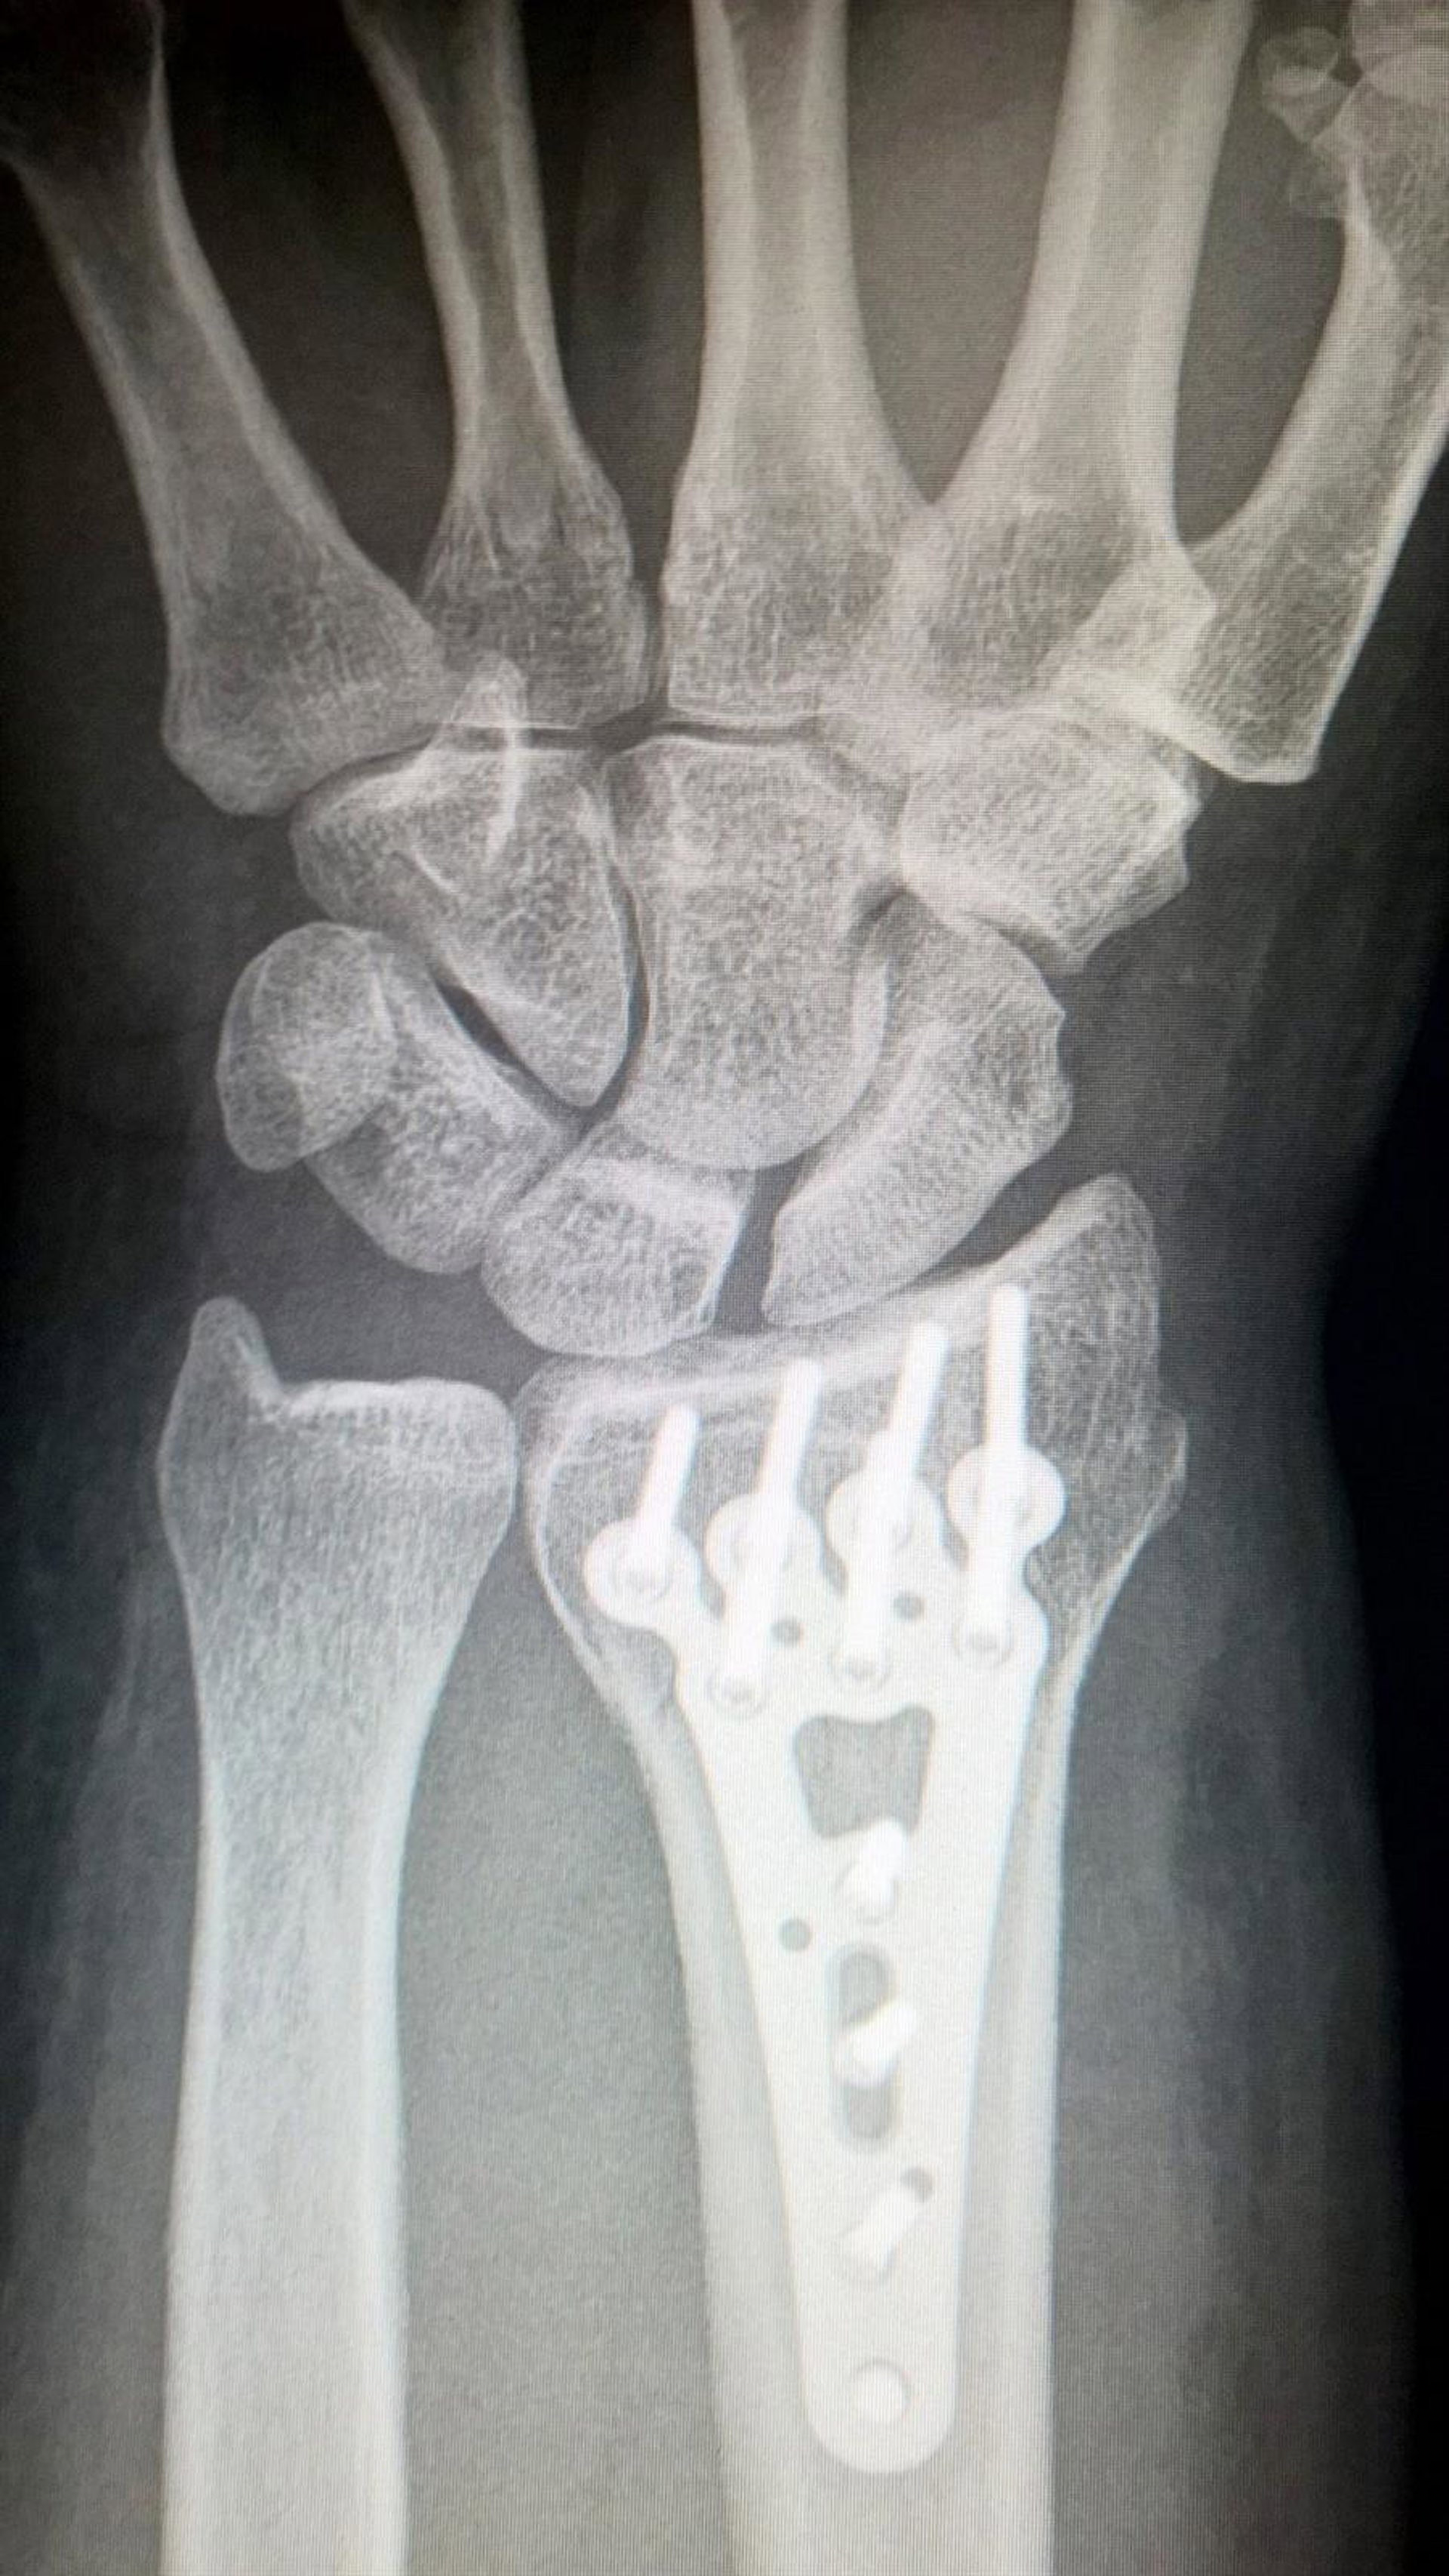

Distracción ósea.

Concretamente, el estudio se ha centrado en la osteogénesis por distracción ósea, un procedimiento de reconstrucción en el que se utiliza un elemento externo denominado distractor que separa gradualmente el hueso. Este mecanismo transmite fuerzas de tracción sobre el callo que se va formando para conectar la fractura y así consigue un estiramiento que produce la formación de nuevo tejido entre las superficies de los segmentos separados.

Es en el tejido generado durante la distracción ósea, donde la punta de diamante ejerce una presión en distintas localizaciones analizando las características mecánicas del nuevo tejido que se va creando. De esta manera, la información que se obtiene en cada estadio podría contribuir a determinar si el tratamiento que se ha establecido es el adecuado o no.